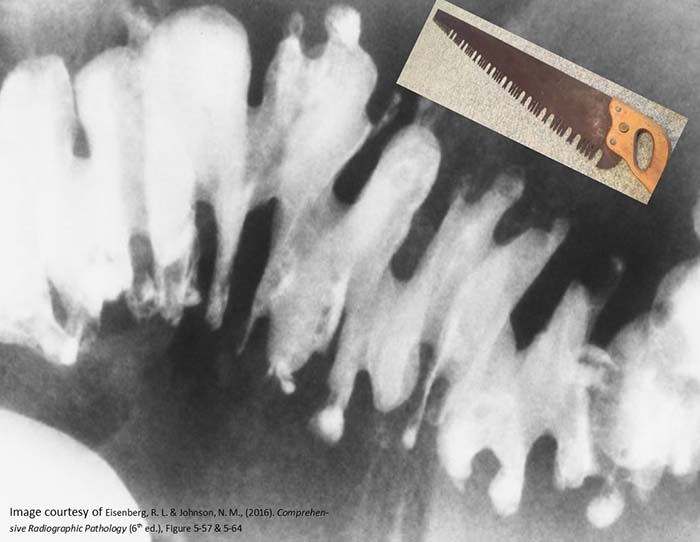

What is intussusception?

Telescoping of a proximal bowel segment into a distal segment, causing obstruction.

Why is intussusception dangerous?

It compresses the mesentery, cutting off blood supply and causing necrosis.

Where does intussusception most commonly occur in children?

At the ileocecal valve.

What is 'red currant jelly' stool?

Stool mixed with blood and mucus, classic for pediatric intussusception.